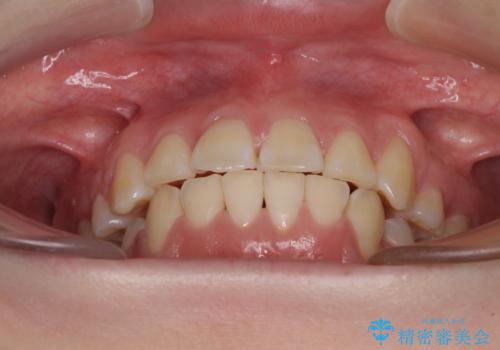

歯列はきれいに整いますが、歯肉ラインは治療前の歯肉の位置を踏襲します。

特に八重歯であった歯は歯冠が長く見えますので、改善を希望される場合には、歯肉移植術を行う必要があります。